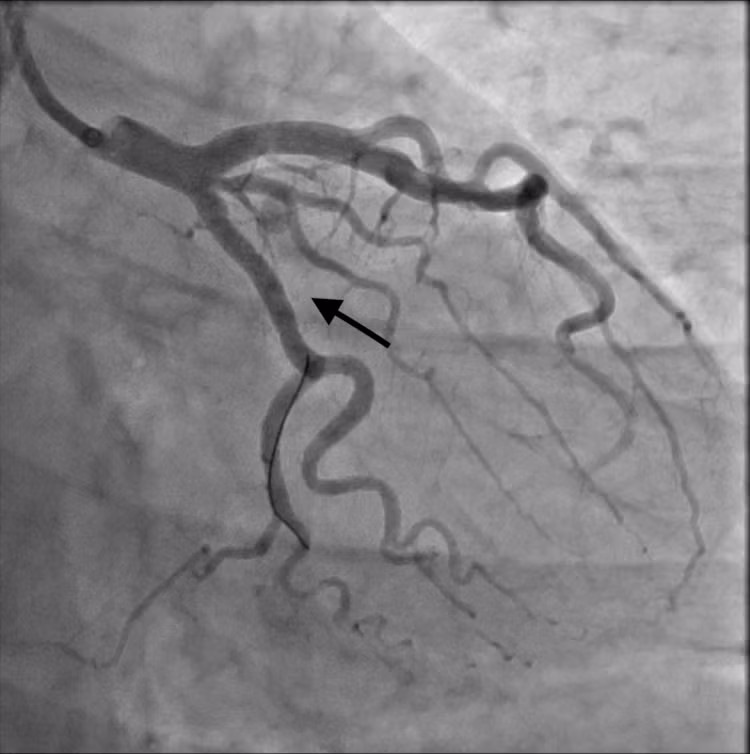

| Ekip can thiệp mạch - Ảnh BVCC |

Để giải quyết triệt để bệnh, các bác sĩ Khoa Can Thiệp Tim Mạch đã tiến hành hội chẩn và quyết định chụp, can thiệp động mạch vành dưới sự hỗ trợ của hệ thống chụp mạch số hoá (DSA) hiện đại.

Chính vì thế, chúng tôi đã tư vấn gia đình bệnh nhân và quyết định đặt 01 covered stent đoạn gần nhánh mũ chặn lỗ vào khối giả phình, giúp làm giảm nguy cơ vỡ giả phình trong tương lai cho bệnh nhân.”